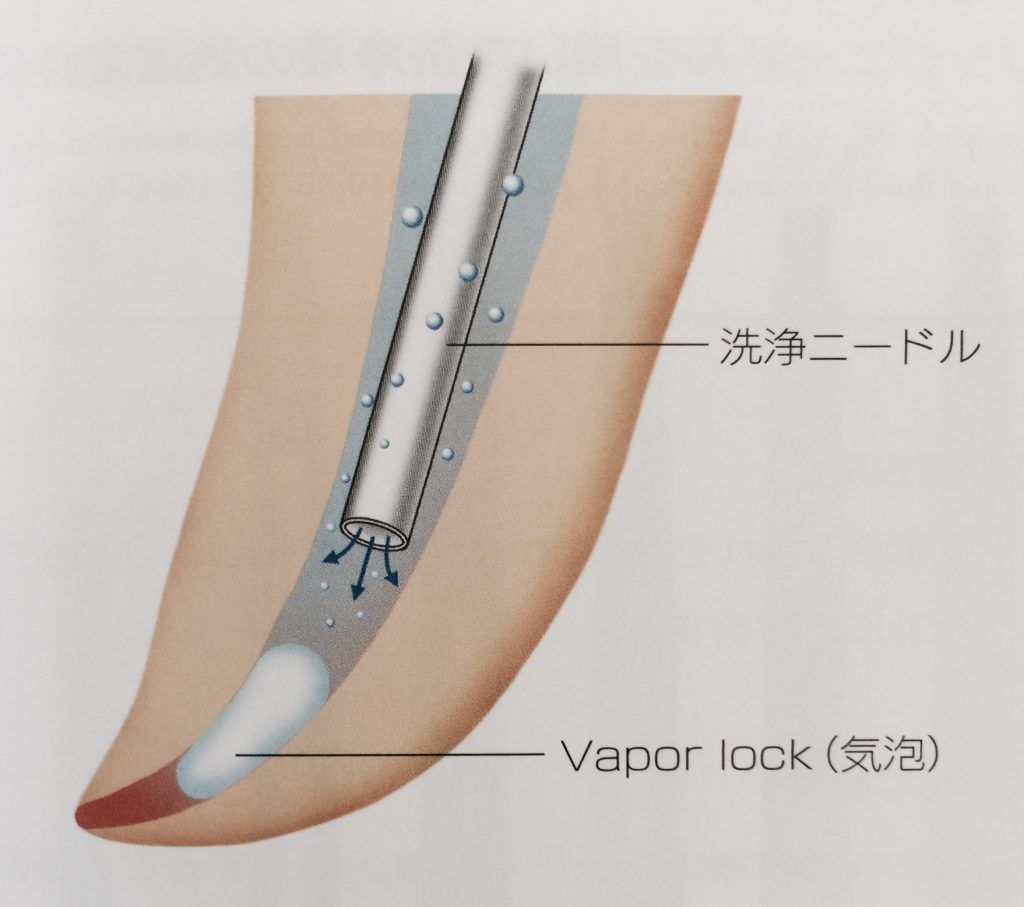

根管洗浄を行っても根管洗浄剤は細部は到達しない

研究によると、根の先の部分での拡大のサイズは#35(350μm)くらいであれば洗浄液が到達するとされています。

それ以下のサイズでは気泡(Vapor Lock)により、洗浄液の根尖への到達を阻害してしまう可能性がある。

写真は「歯内療法の迷信と真実」牛窪先生、山本信一先生、神戸良先生著より

この事実から根管の細い狭いところまで拡大は出来ないので洗浄液は到達出来ないという結論が導かれます。